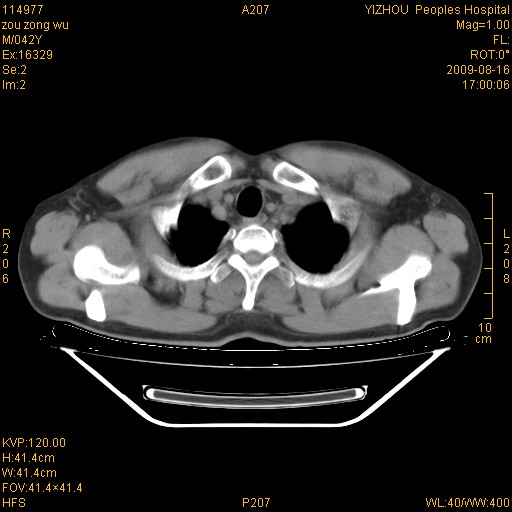

以下是引用zjzjr在2009-8-17 10:42:00的发言:[br]右侧间质性肺炎伴纤维化,右肺下叶肺囊肿伴感染(不除外外伤后引起),右肺野及胸壁软组织\\肝内见多发斑点状,中枪了吧.右侧胸膜肥厚\\粘连.